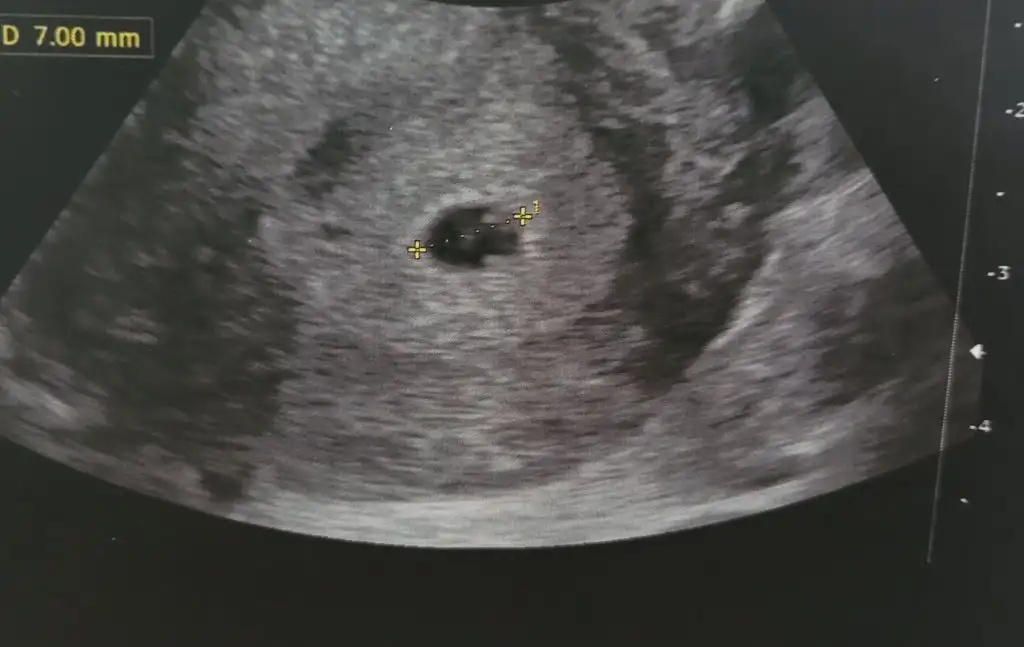

Atmış mıydın ultrason resmi bakalımRamzi , çin takvimi ve bu hesaplama erkek diyor . Ama ben kız hıssedıyorummm

Canımcım sırasıyla attım. Bakalım sen nedıcenAtmış mıydın ultrason resmi bakalım

Kız diyorumCanımcım sırasıyla attım. Bakalım sen nedıcen